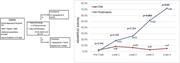

Effects of daratumumab on natural killer cells and impact on clinical outcomes in relapsed or refractory multiple myeloma

Tineke Casneuf,Xu Steven Xu,Homer C. Adams, III,Amy E. Axel,Christopher Chiu,Imran Khan,Tahamtan Ahmadi,Xiaoyu Yan,Sagar Lonial,Torben Plesner,Henk M. Lokhorst,Niels W. C. J. van de Donk,Pamela L. Clemens,A. Kate Sasser